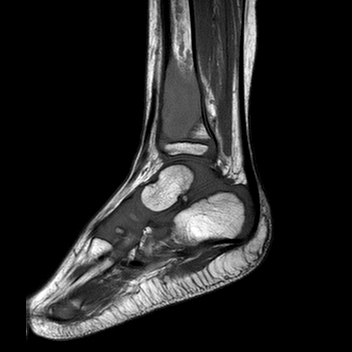

An x-ray and subsequent MRI were ordered of the ankle which demonstrated an expansile lytic lesion involving the metaphysis of the distal tibia measuring approximately 3.4 x 2.2 cm (Figure 1 and 2). The margins of this lesion are indistinct, and there is cortical irregularity at the anterior and lateral aspect of the distal metaphysis of the tibia, likely representing a pathologic fracture. The differential diagnosis includes infection, aneurysmal bone cyst, nonossifying fibroma, osteoblastoma and histiocytosis.

Figure 2. MRI demonstrating the lytic lesion involving the metaphysis of the distal tibia.

In a study by Inyang et al, when PHE involved bone, imaging would demonstrate multiple to innumerable discontinuous tumors throughout the affected bone, involving the cortex and/or medullary cavity of the epiphysis, metaphysis, or diaphysis. On x-ray and computed tomography, the lesions appeared as well circumscribed, lobulated and lytic, with a sclerotic rim on some of the lesions. On magnetic resonance imaging, T1-weighted images would appear dark, and T2-weighted images would appear hyperintense.